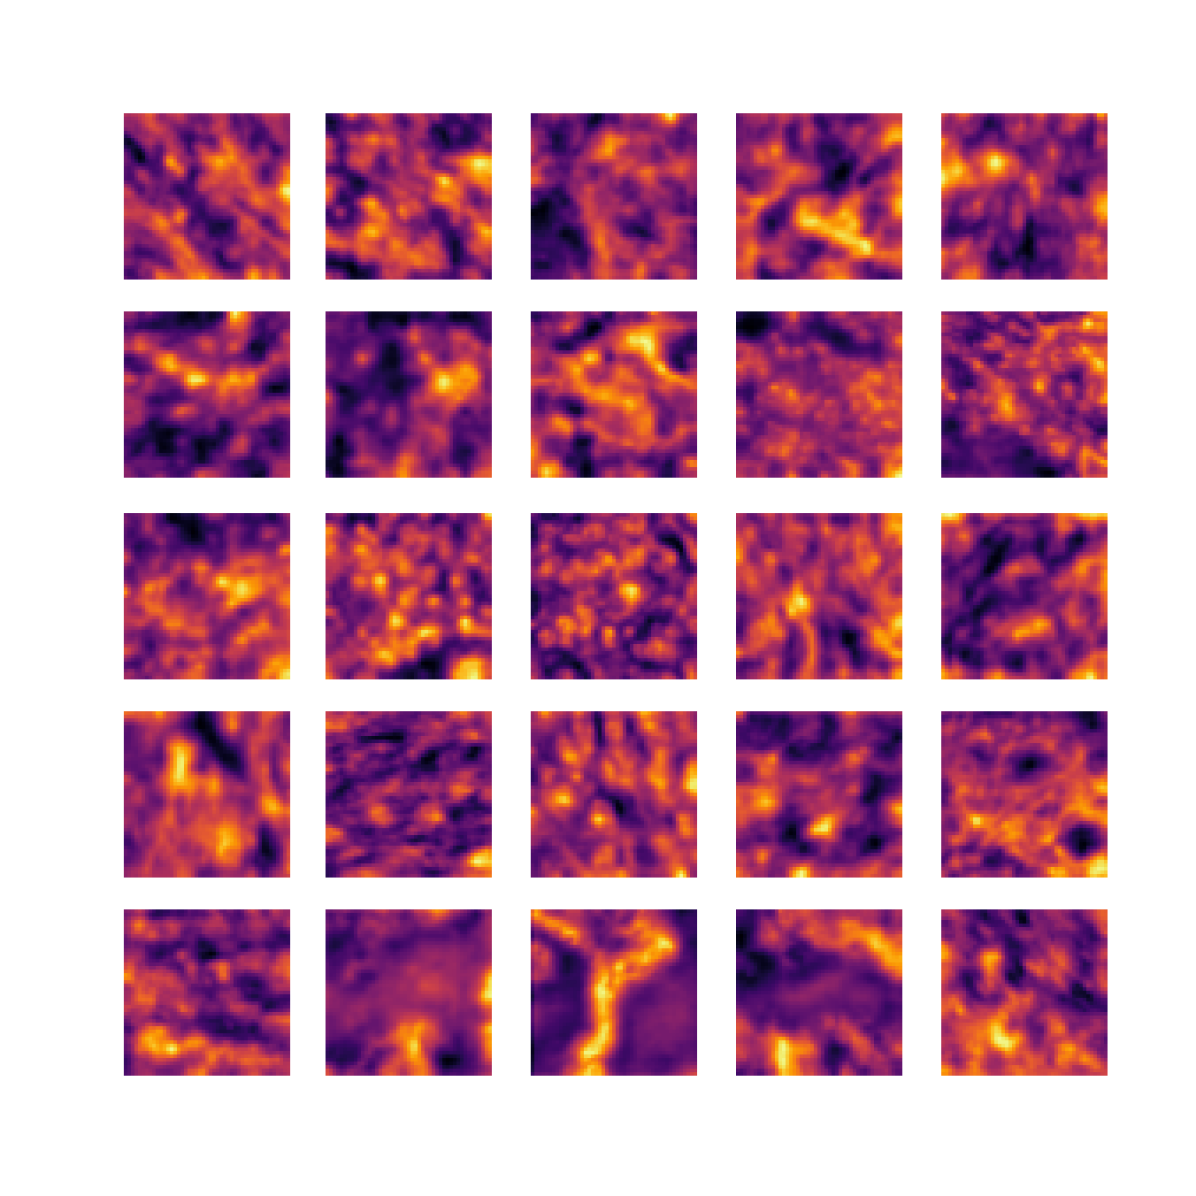

We also analyse the activation maps for each model using GradCAM as described in section S3. This offers more insight into the areas of the image which are contributing most heavily to the models’ representations. In Figure 4(b) we present some representative examples, however, a larger selection which was chosen at random is presented in Figures S10 to S25. The larger selection makes it easier to see the emergent patterns, including that privileged Siamese models tend to mainly identify features which are strongly present in both inputs, while unprivileged Siamese models tend to learn more diffuse features that are not specific to one cell phenotype or image region. TriDeNT ♆ incorporates both sets of features, learning both features specific to the privileged data and more the general features associated with unprivileged Siamese networks.

We can see in Figure 4(b) panel A that for ERG, the privileged Siamese model focuses almost exclusively on any nuclei which could be endothelial cells. As there are very few endothelial cells in the dataset, it could be an effective strategy to identify anything that could potentially be an endothelial cell to minimise the difference between the representations of the H&E model and the IF mask model. In the corresponding unprivileged Siamese image, we see that the model identifies some of these nuclei, albeit less strongly, but also focuses heavily on the other tissue and even the background, while strongly fixating on two spots of debris in the center of the image. This model has less ‘incentive’ to learn the weak features related to endothelial cells as these occur rarely and are not easy to detect, while more generic strong features such as the presence of connective tissue and the prevalence of background are more common and predictable from augmented images. We see that TriDeNT ♆ combines these two feature sets, strongly identifying nuclei while also identifying the connective tissue.

In panel C we see a similar pattern, with the privileged Siamese model fixating solely on the nuclei, while the TriDeNT ♆ model takes a more balanced approach. The unprivileged Siamese model appears to focus on a single cluster of nuclei while neglecting others, and similarly identifies an area of fibroblasts with its distinctive pattern but does not others.

In contrast to panels A and C which represent models with poor privileged Siamese results, panels B and D represent models whose privileged Siamese results were comparable to both TriDeNT ♆ and even the supervised baseline. It is therefore interesting to note that there are far more similarities between the privileged Siamese and TriDeNT ♆ models in both cases. Particularly in panel B, TriDeNT ♆ and the privileged Siamese model return virtually identical heatmaps, with both strongly identifying epithelial nuclei and neglecting the same areas of connective tissue. The unprivileged model in this case appears to focus solely on the centre of the image, giving a significantly different heatmap to the other panels.

Panel D again shows the previous pattern, with the privileged Siamese model identifying the features strongly present in the privileged data – fibroblasts – while neglecting the nuclei present. TriDeNT ♆ also strongly identifies the connective tissue, but, unlike the privileged Siamese model, does not completely neglect the nuclei. The unprivileged Siamese model primarily identifies background, and does not appear to identify the nuclei in this example.